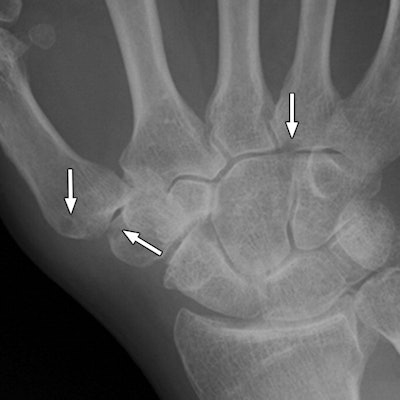

MRI has had more success in visually detecting bone erosion before the condition can be seen on conventional x-rays. Meanwhile, tomosynthesis has the ability to evaluate subtle fractures and joint surface, as well as image metallic implants.

Tomosynthesis and MRI detected significantly more bone erosions than conventional radiography, the researchers found. The detection rate for tomosynthesis was 36.1%, compared with 36.7% for MRI and 26.5% for digital radiography.

Based on the results, "tomosynthesis is far superior to radiography and is comparable to MRI for the detection of bone erosion in patients with rheumatoid arthritis," Aoki and colleagues wrote.